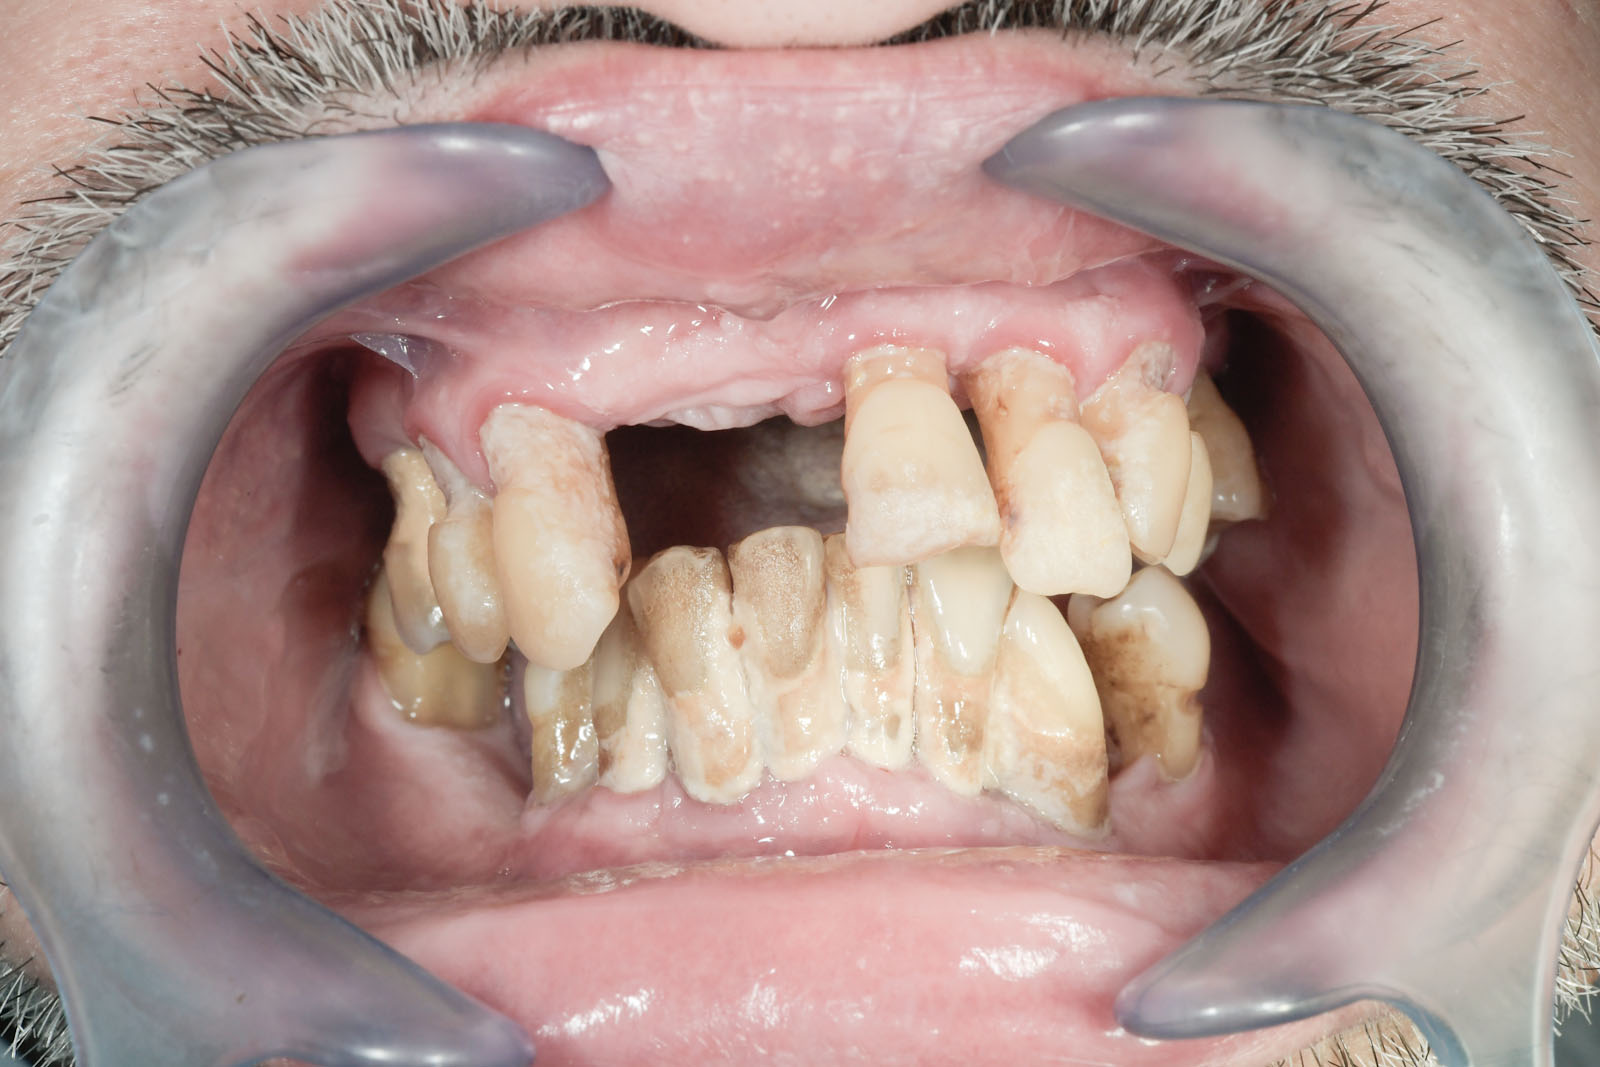

Niewłaściwa codzienna higiena jamy ustnej prowadzi do powstawania płytki nazębnej. Nieusuwana płytka nazębna ulega mineralizacji (zwapnieniu) pod wpływem soli mineralnych zawartych w ślinie, przekształcając się w kamień nazębny. Jest on nie tylko nieestetyczny, lecz przede wszystkim stanowi zagrożenie dla organizmu z uwagi na stacjonujące w nim bakterie. Obecność bakterii i kamienia nazębnego prowadzi do rozwoju chorób dziąseł i przyzębia, w efekcie do rozchwiania zębów, co w konsekwencji może doprowadzić nawet do ich utraty.